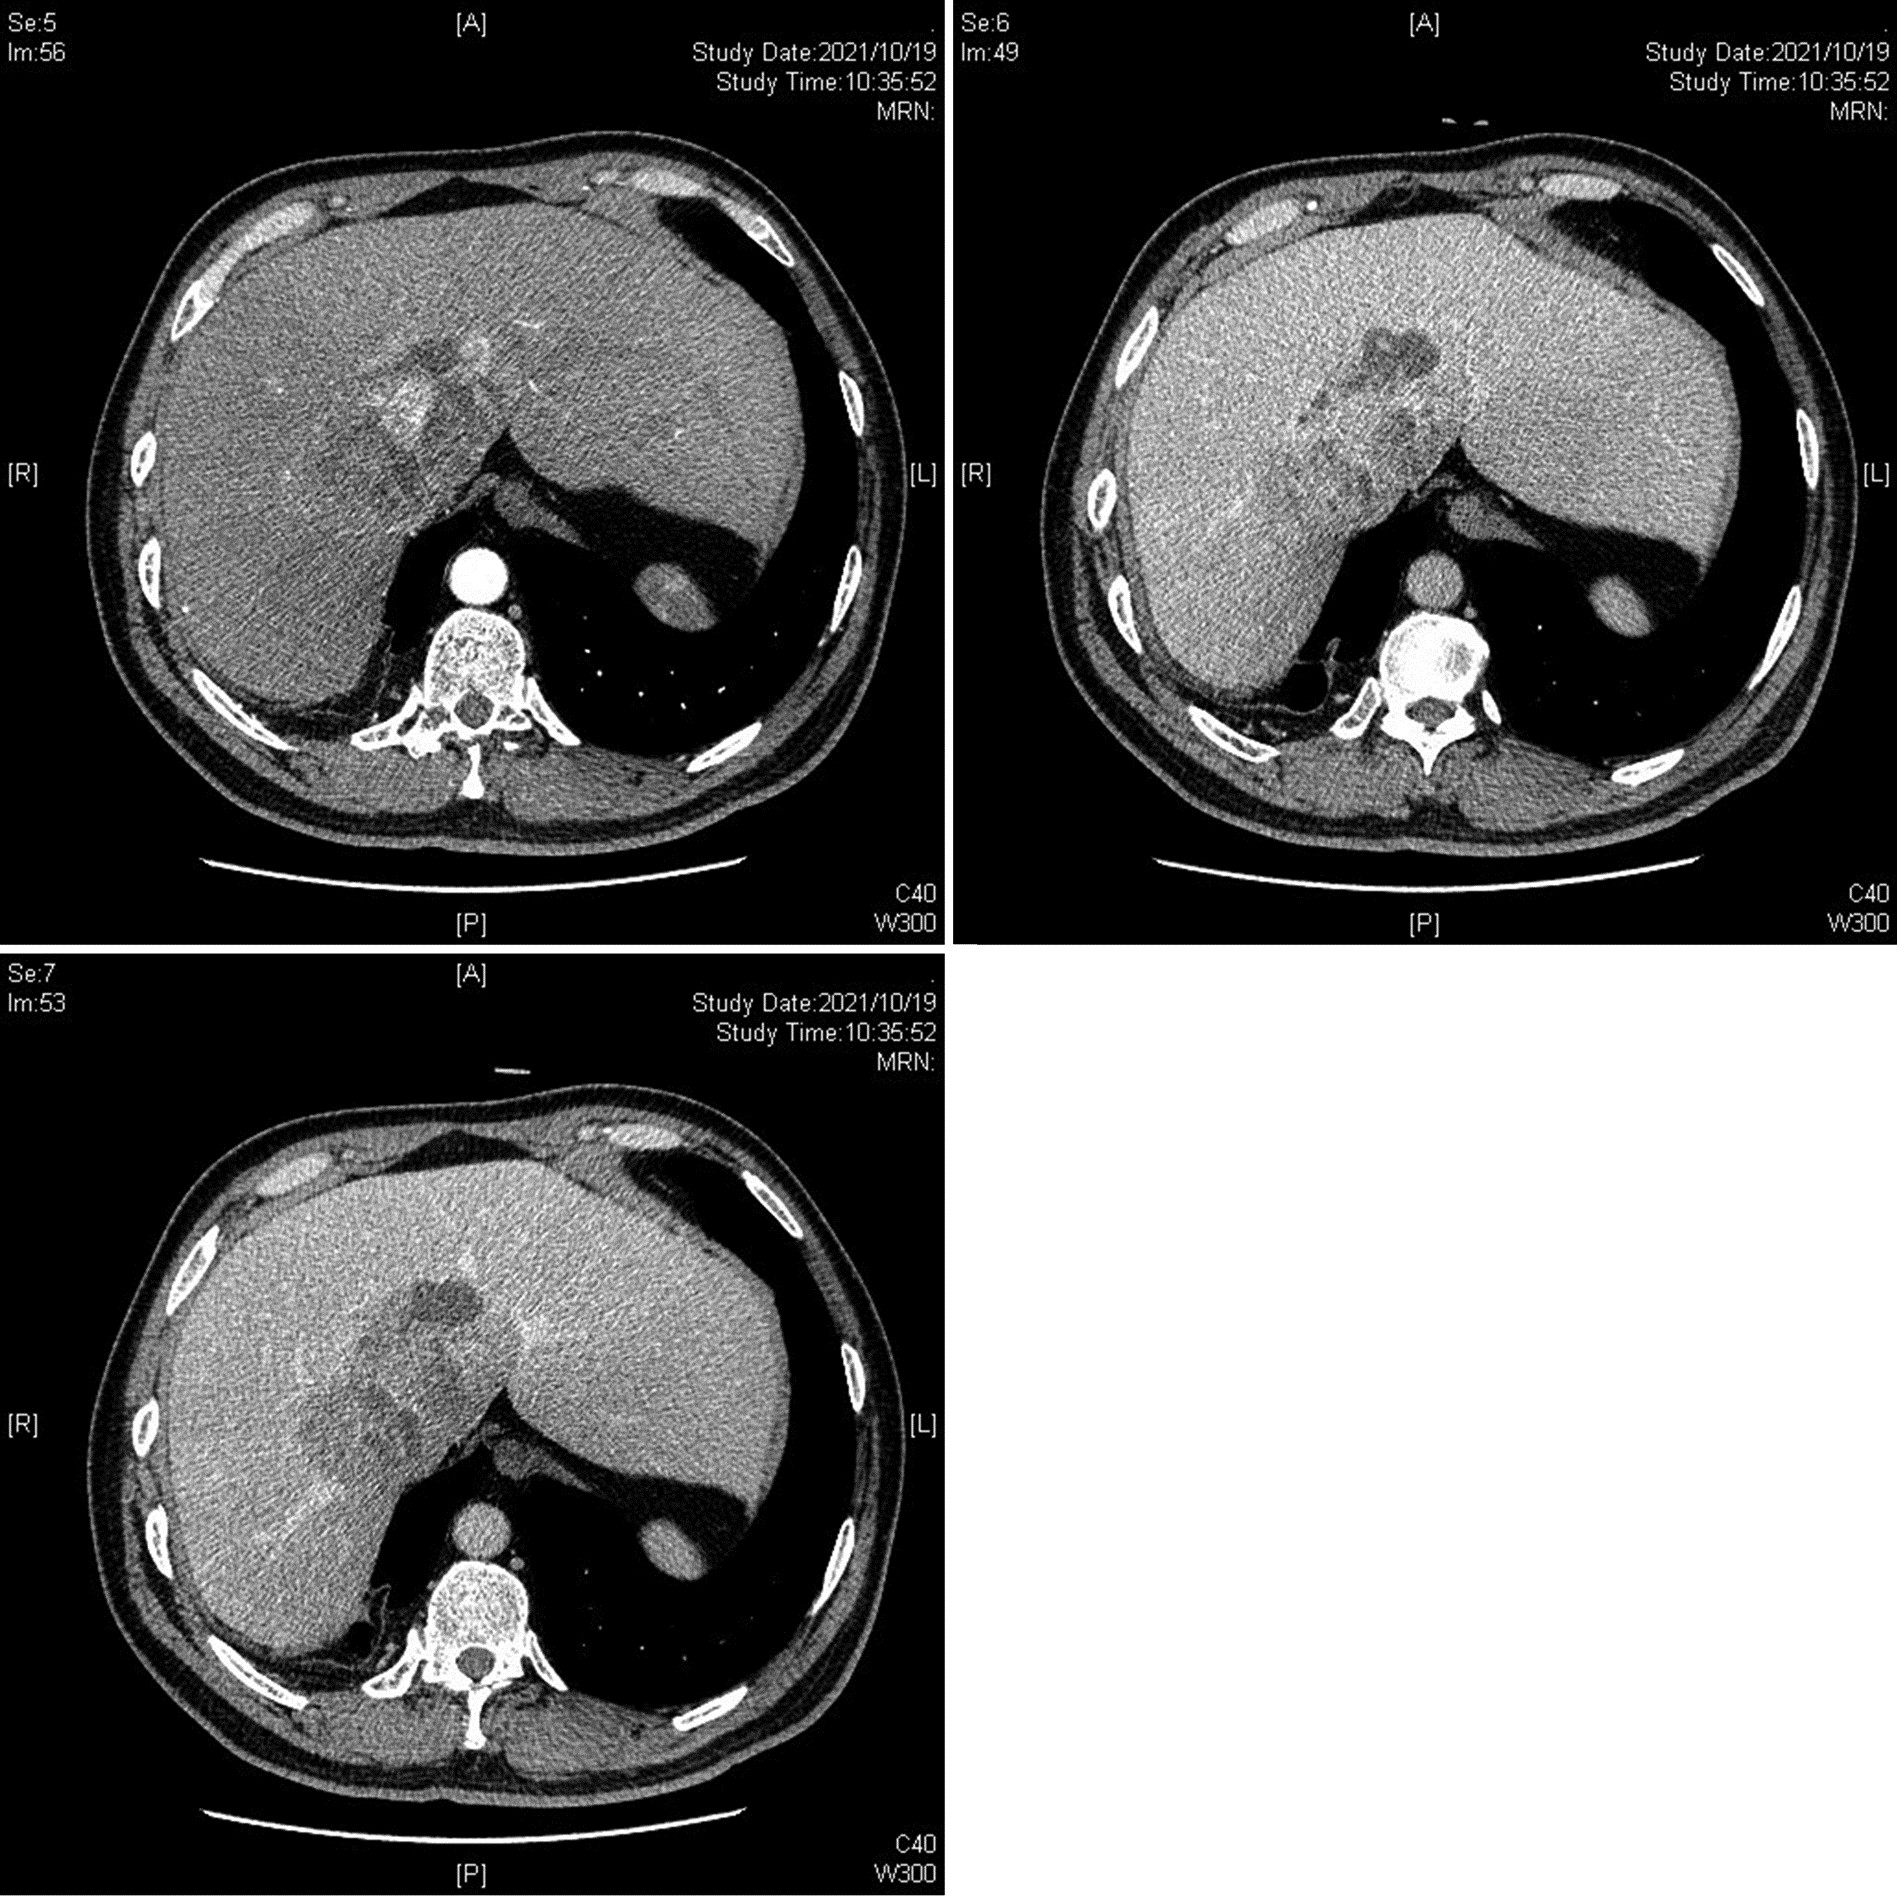

先天性左肝缺如合并肝细胞癌1例报告

王海林, 李敬东, 武国

2023, 39(6): 1408-1410. DOI: 10.3969/j.issn.1001-5256.2023.06.023

摘要(836) HTML (197) PDF (2003KB)(59)

摘要: